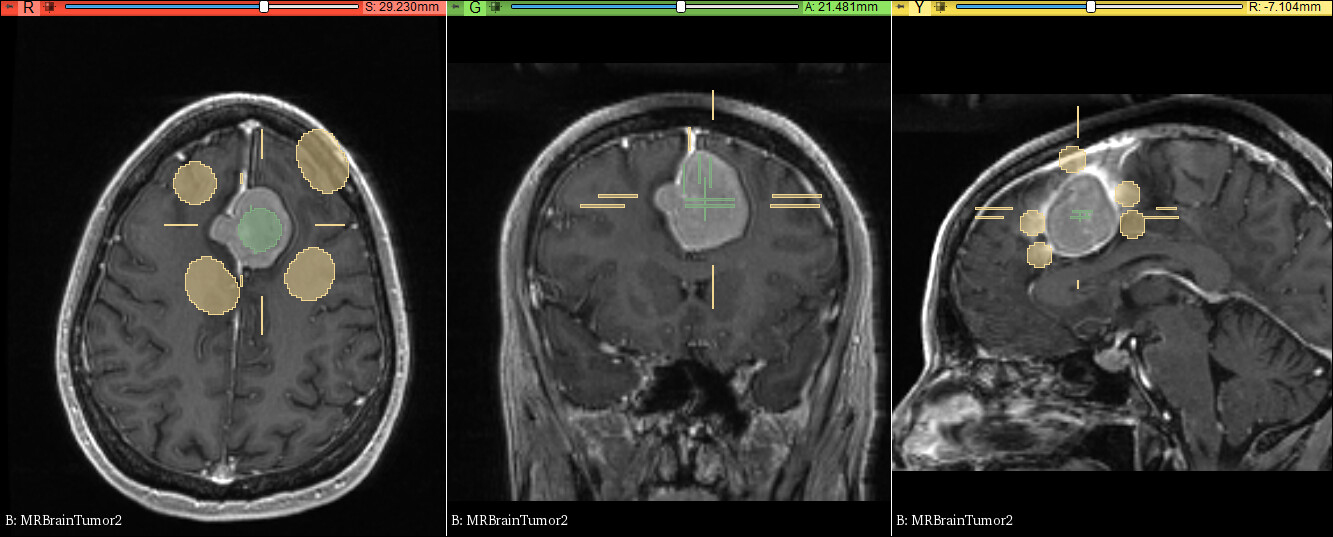

练习数据:示例数据MRBrainTumor2

• 应用笔刷或画笔涂画要分割的部分作为种子

• 换一种颜色涂画要分割组织的周围部分

• 点击预览观察分割结果是否正确

• 在错误的分割区域增加更多的种子,结果自动更新

• 可以定义结构的平滑度,从而可以防止泄漏